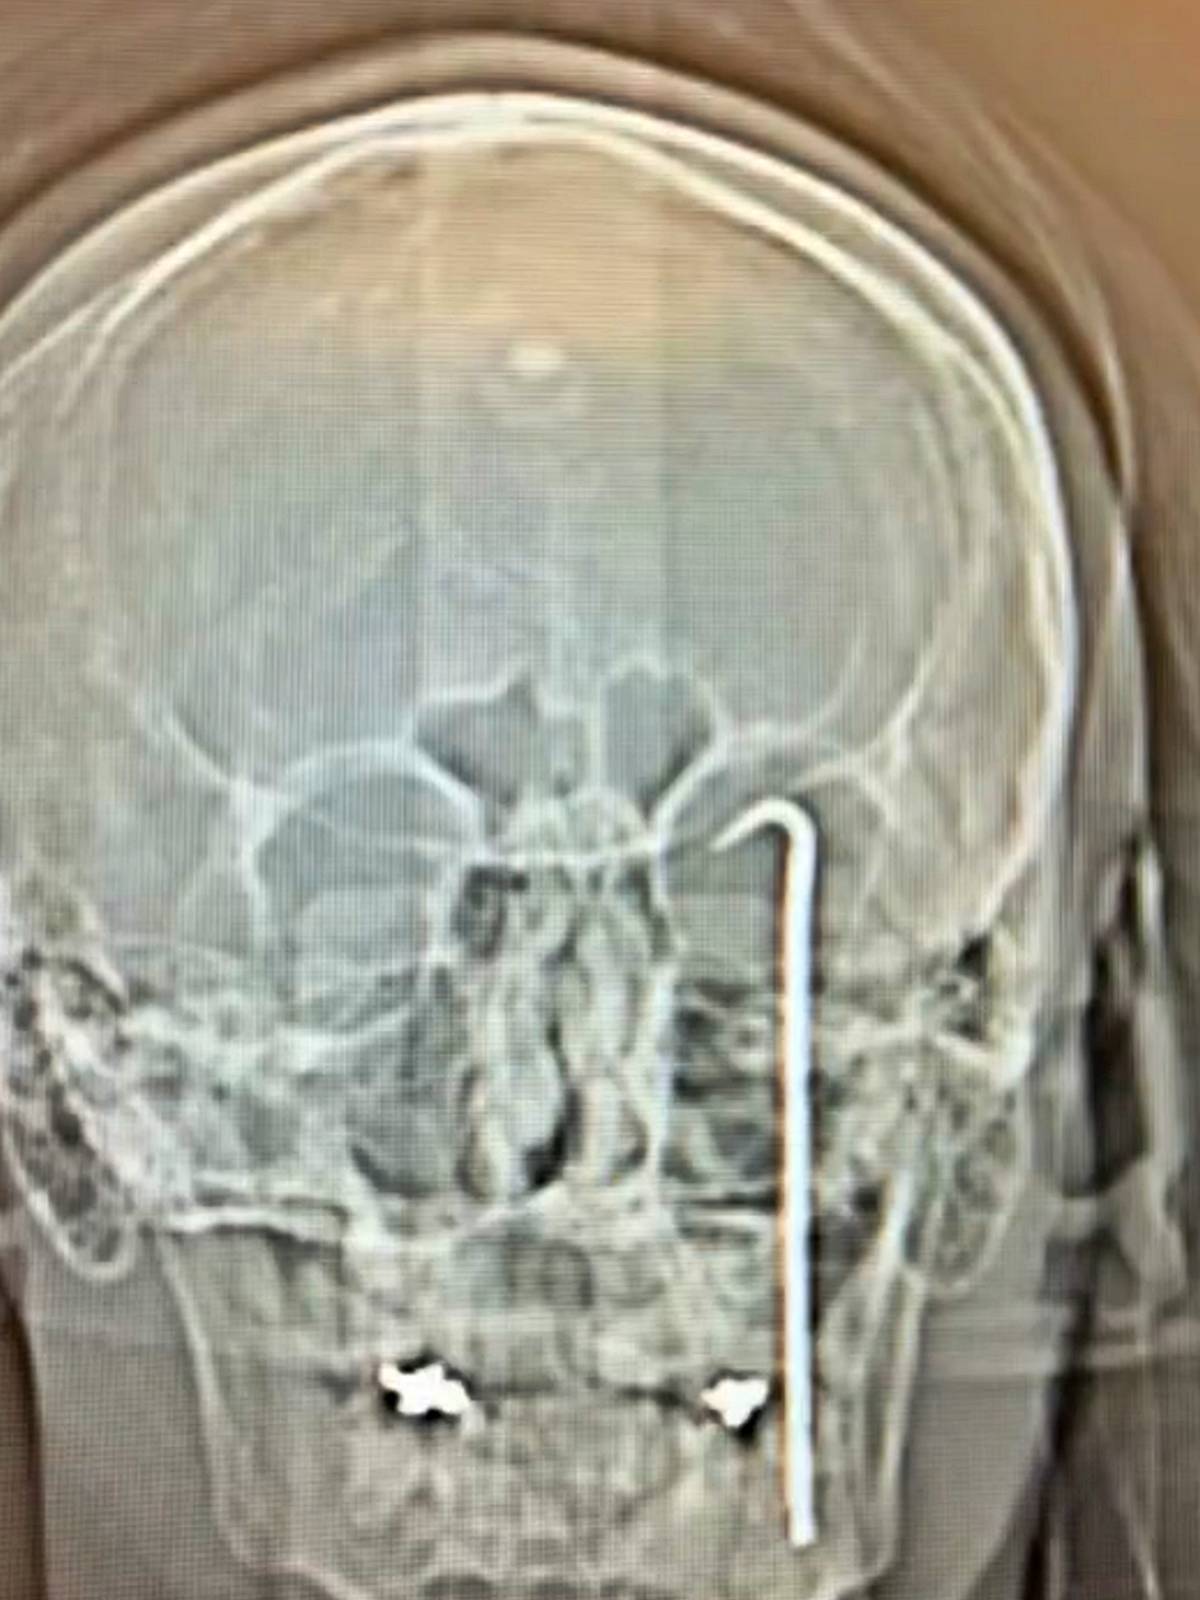

Görüntülerin devamında, hastanede tedavi altına alınan teknisyenin gözünden giren aletin, kafatasına saplandığı röntgen ve MR görüntüleri ile ortaya çıkıyor.